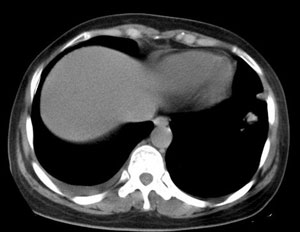

女性,30岁。

病史为胸痛20多天,无畏寒发热,无消瘦,无咳嗽咳痰。总之症状很逍遥。

临床以胸痛待查收住入院。

双肺野可见散在大小不等结节及肿块影,内密度不均匀,边缘部分清,部分欠清,纵隔未见明显肿大淋巴结.右侧胸腔少理积液.结合临床,考虑韦格肉芽肿可能吧,巨淋巴增生,结节病,特殊感染都要考虑.转移瘤临床不象.

本病例特点如下:

1.青年女性,以胸痛20多天就诊,无呼吸道及感染临床症状体征,无原发肿瘤病史;

2.肺ct表现为两肺多发大小不等结节影,大结节位于肺尖部,小结节多位于肺外带胸膜下,大结节内可见支气管充气征,周围可见月晕征(指在结节状或肉芽肿样病灶周围呈环形磨玻璃影),右肺门及腔静脉后可见小淋巴结,右侧胸腔内少量液体。

两肺散在分布大小不等的肿块及结节影,边缘毛糙,有分叶、毛刺,病灶密度不均匀,可见支气管充气相与空泡征。病变大多位于胸膜下,可见胸膜凹陷及胸腔积液。气管腔静脉间可见小结节影。

病人临床仅为胸痛,暂不考虑感染性病变。

考虑多发结节型细支气管肺泡癌。

考虑肺真霉菌病;心脏增大,肺动脉增宽